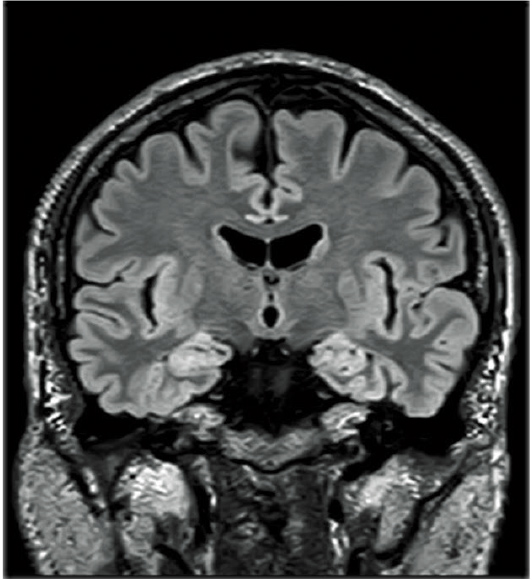

isoFSE, isovokseller için yüksek hızlı bir 3D görüntüleme işlevidir. FSE’nin yeniden netleme pulslarının çevirme açıları, MultiEchoes’un sinyal gücü dalgalanmalarından kaynaklanan etkiyi bastırmak ve yüksek çözünürlüklü 3D görüntüleme sağlamak için kullanılmaktadır. Bu uygulama modellerinin optimizasyonu, T1WI, T2WI ve FLAIR görüntüleri ile elde edilen yüksek kontrastlarla sonuçlanır.

Görüntülemede elde edilen yüksek uzamsal çözünürlüklü hacim verileri, MPR işlemede herhangi bir çapraz görüntülerini yeniden oluşturmak için kullanılabilir.Akıllı ÇALIŞMA